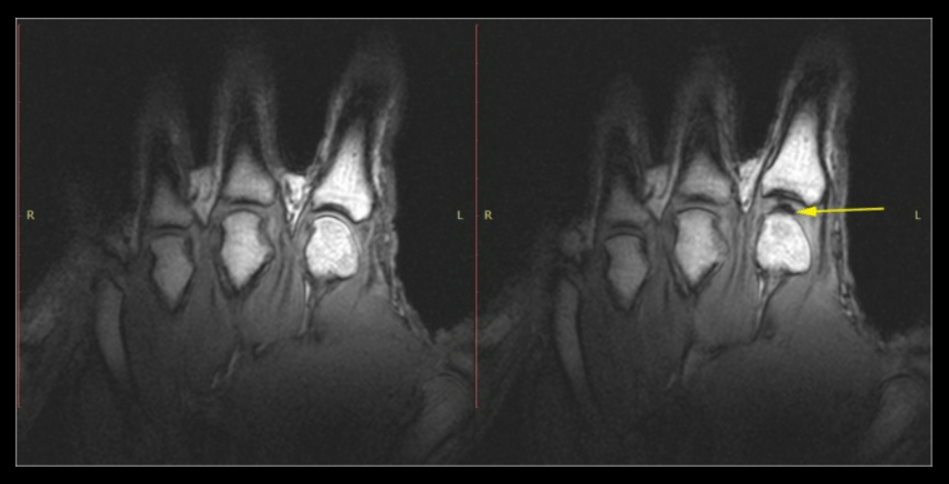

Слева: рука в покое перед растрескиванием. Справа: та же рука после хруста от растяжения. Обратите внимание на тёмную межсуставную полость (жёлтая стрелка). Источник изображения: pubmed.ncbi.nlm.nih.gov

Когда вы резко растягиваете суставы, давление внутри жидкости падает, и возникают газовые полости/пузырьки, которые мгновенно частично схлопываются. Именно этот процесс и даёт характерный звук. Хотя точный момент (образование или частичное схлопывание) ещё обсуждается.